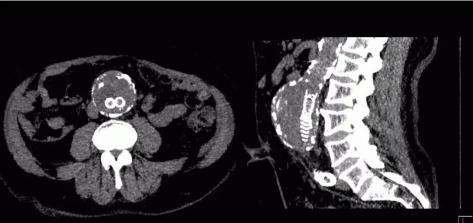

ForceCT转速可达0.25秒/圈,双套球管及探测器交叉90度设计,相当于单源CT 0.125 秒/圈,心脏成像时间分辨率66ms,真正跨越自由心跳门槛100ms,因此可以做到自由心率的心脏冠脉CTA等检查。

西门子独创的Turbo Flash模式,扫描速度达每秒73.7厘米,可在1秒内完成胸腹大血管、头颈心一站式筛查,对胸痛三联征、心脑联合成像、头胸心腹部及全程主动脉等多部位一站式联合扫描等检查都能很好的完成。

无镇静自由呼吸婴儿(1天)主动脉缩窄,70KV,CM:7ml02